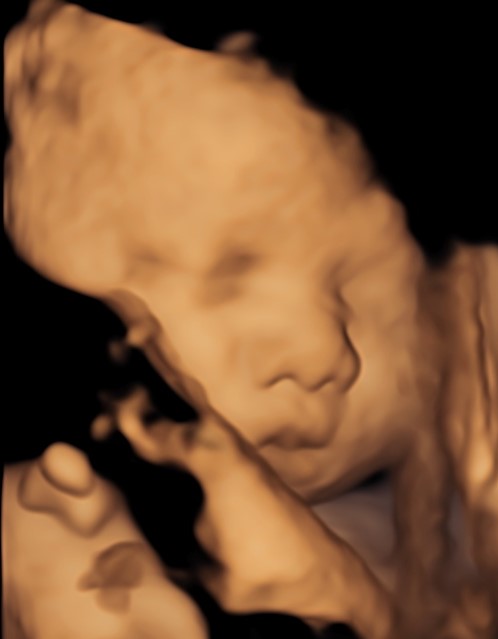

Monmouth County’s First 4D/5D/HD Live Ultrasound Studio

4D/5D/HD Ultrasound Gallery

Gallery